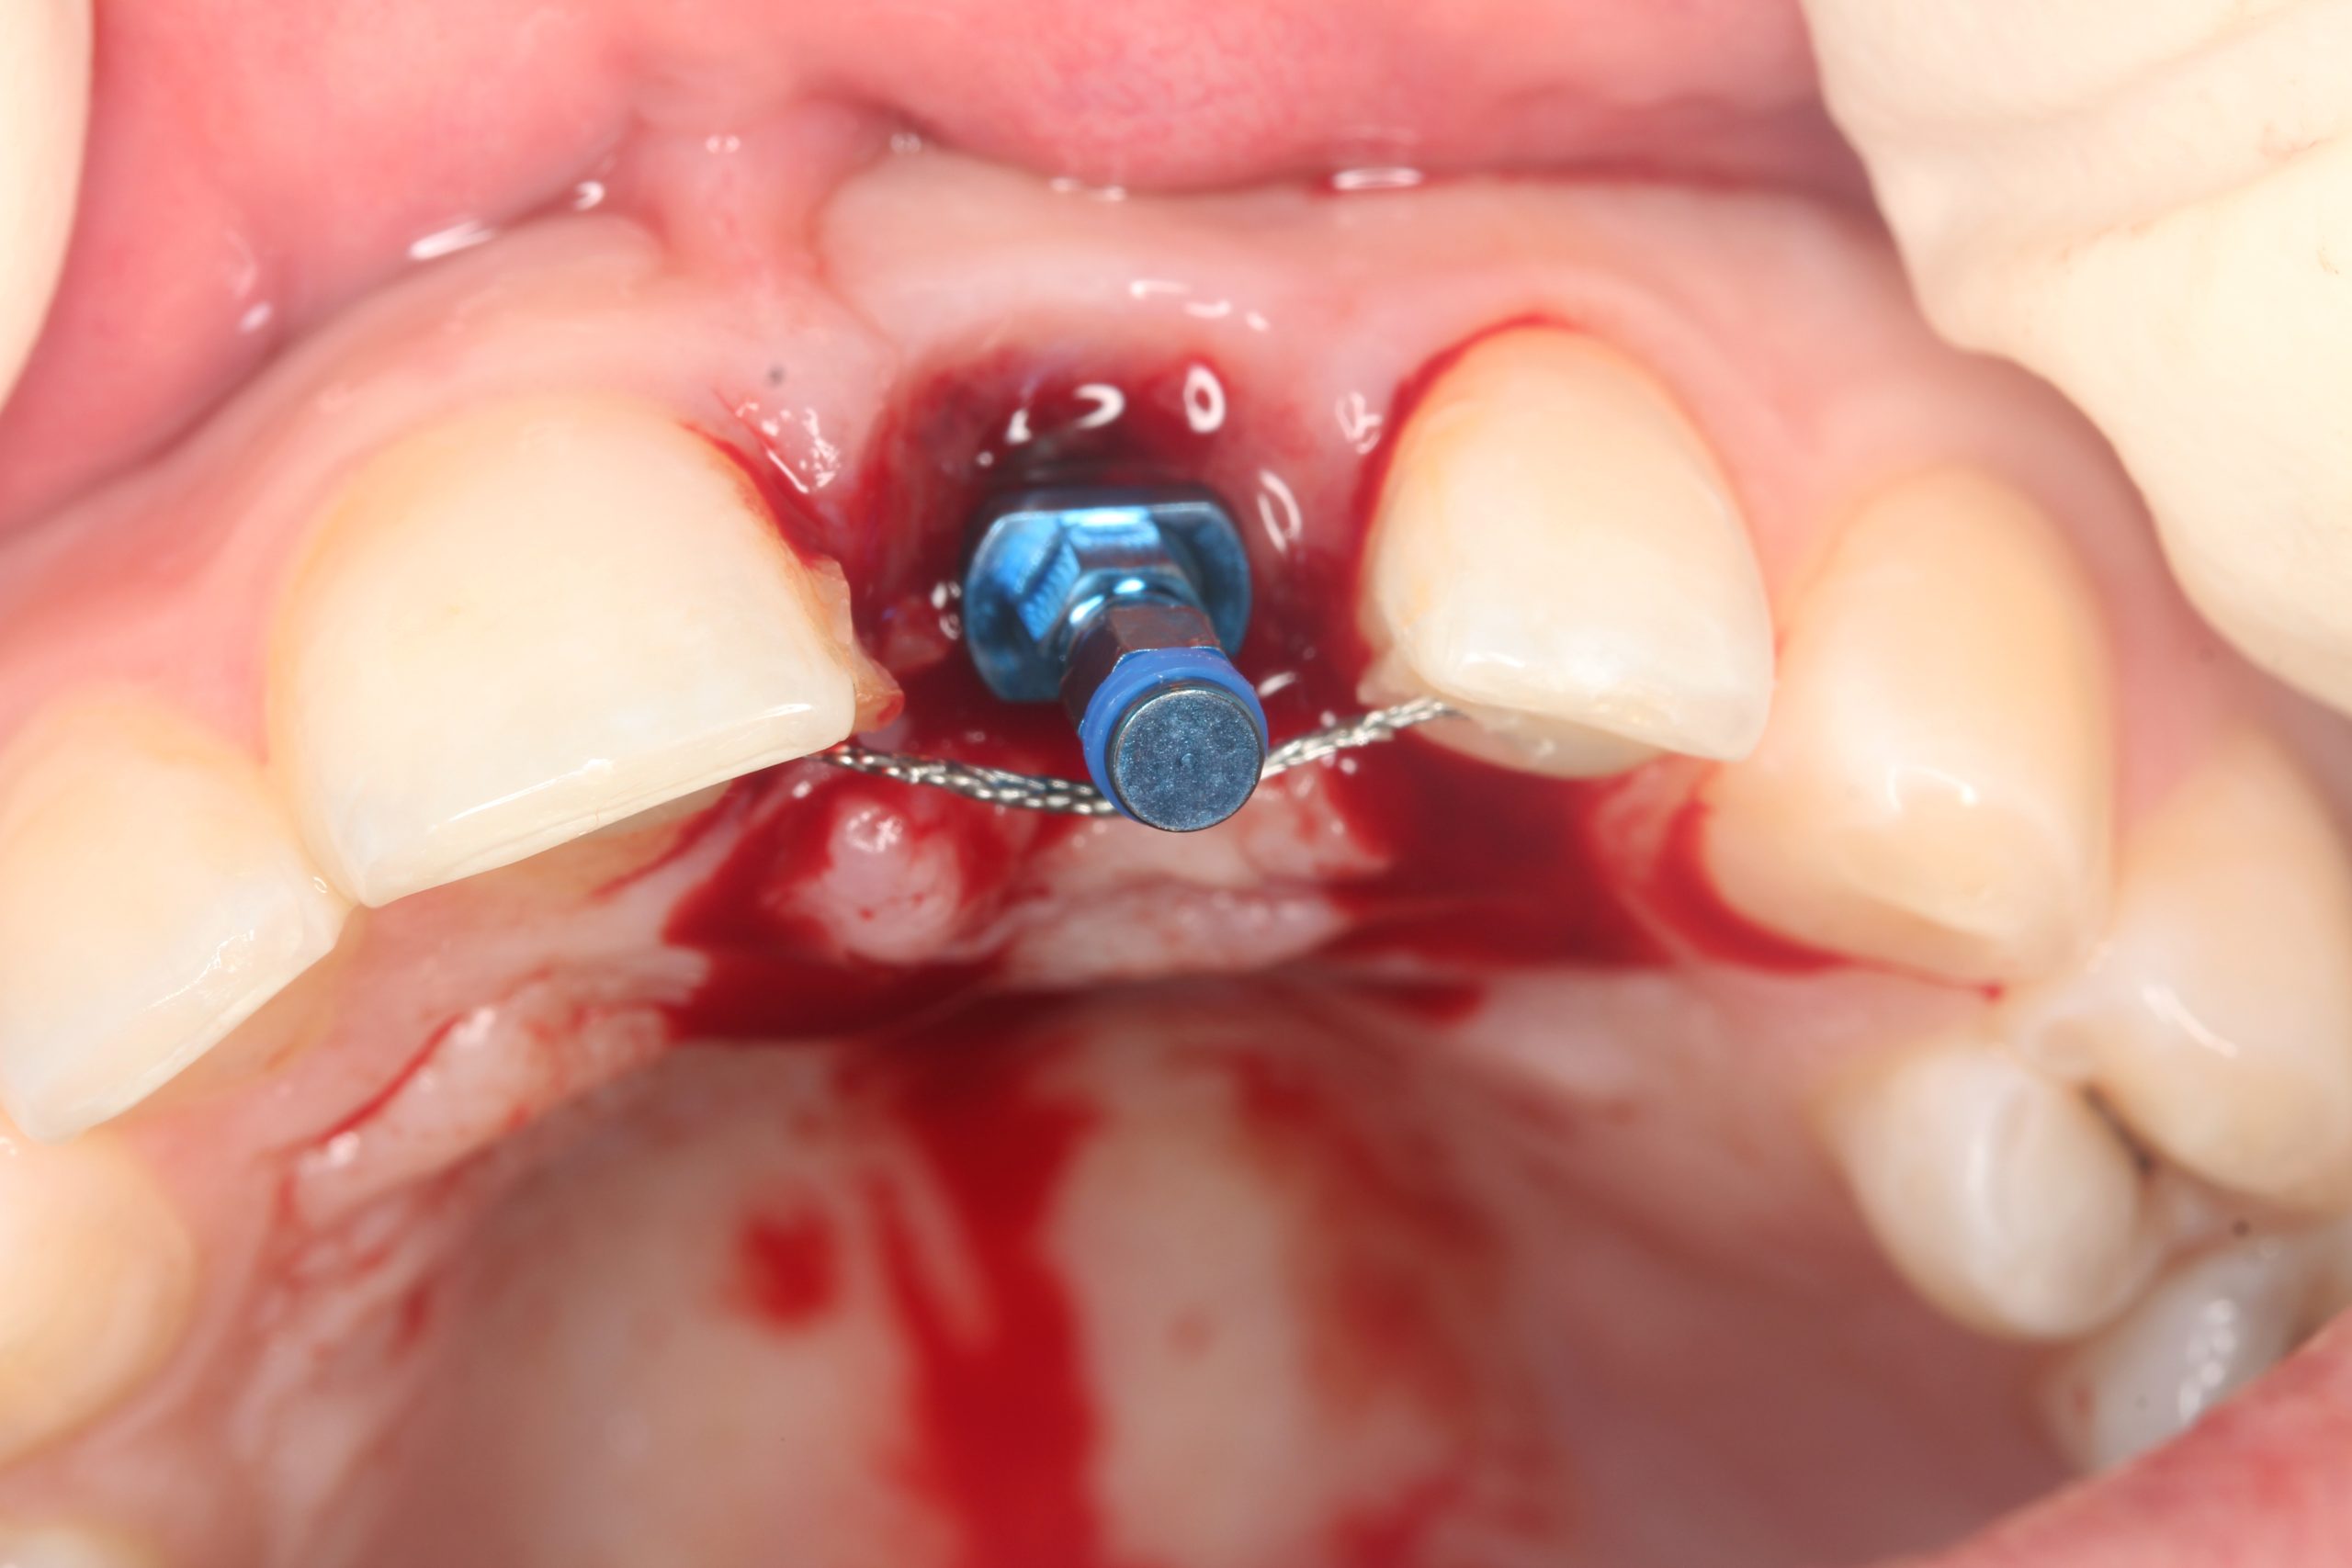

The mucoperiosteal flap was lifted palatally and partially mobilized vestibularly. A 14 mm long BioniQ implant from LASAK with Ø 4 mm was inserted and a temporary abutment was attached after removing the implant carrier.